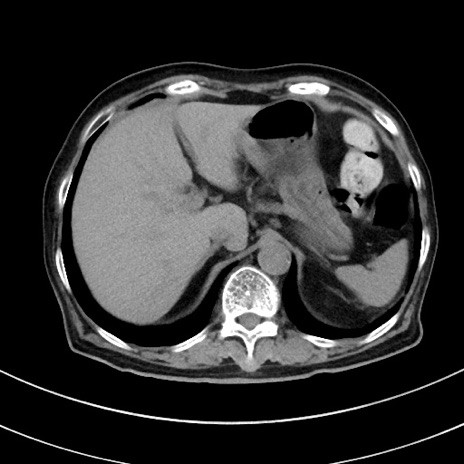

症例33(横断像)

【症例】70歳代 女性

【主訴】心窩部痛

【現病歴】延髄病変の精査・加療にて神経内科入院中。本日より心窩部痛あり。

【既往歴】虫垂炎

【身体所見】右下腹部を中心に圧痛と反跳痛あり。

【データ】WBC 10900、CRP 0.02